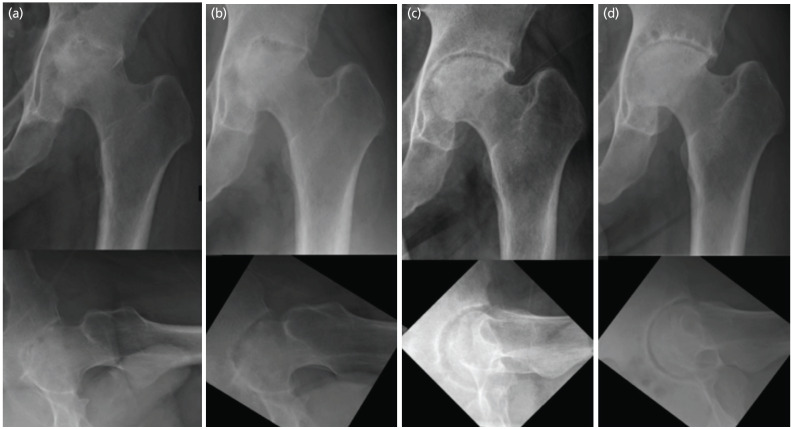

A 31-year-old man presented with abscesses of the left iliacus muscle, adductor muscles and left hip septic arthritis. Following surgical debridement and antibiotics, he remained infection free at 3 years. We present the radiographic evolution of the changes in his left hip . Despite destruction of the hip during initial follow-up, there was remoulding of the proximal femur with changes of avascular necrosis over a 3-year period with good hip function. Hip septic arthritis may result alarming radiographic changes during initial follow-up. Some patients may continue to improve clinically and radiographically in the short term.